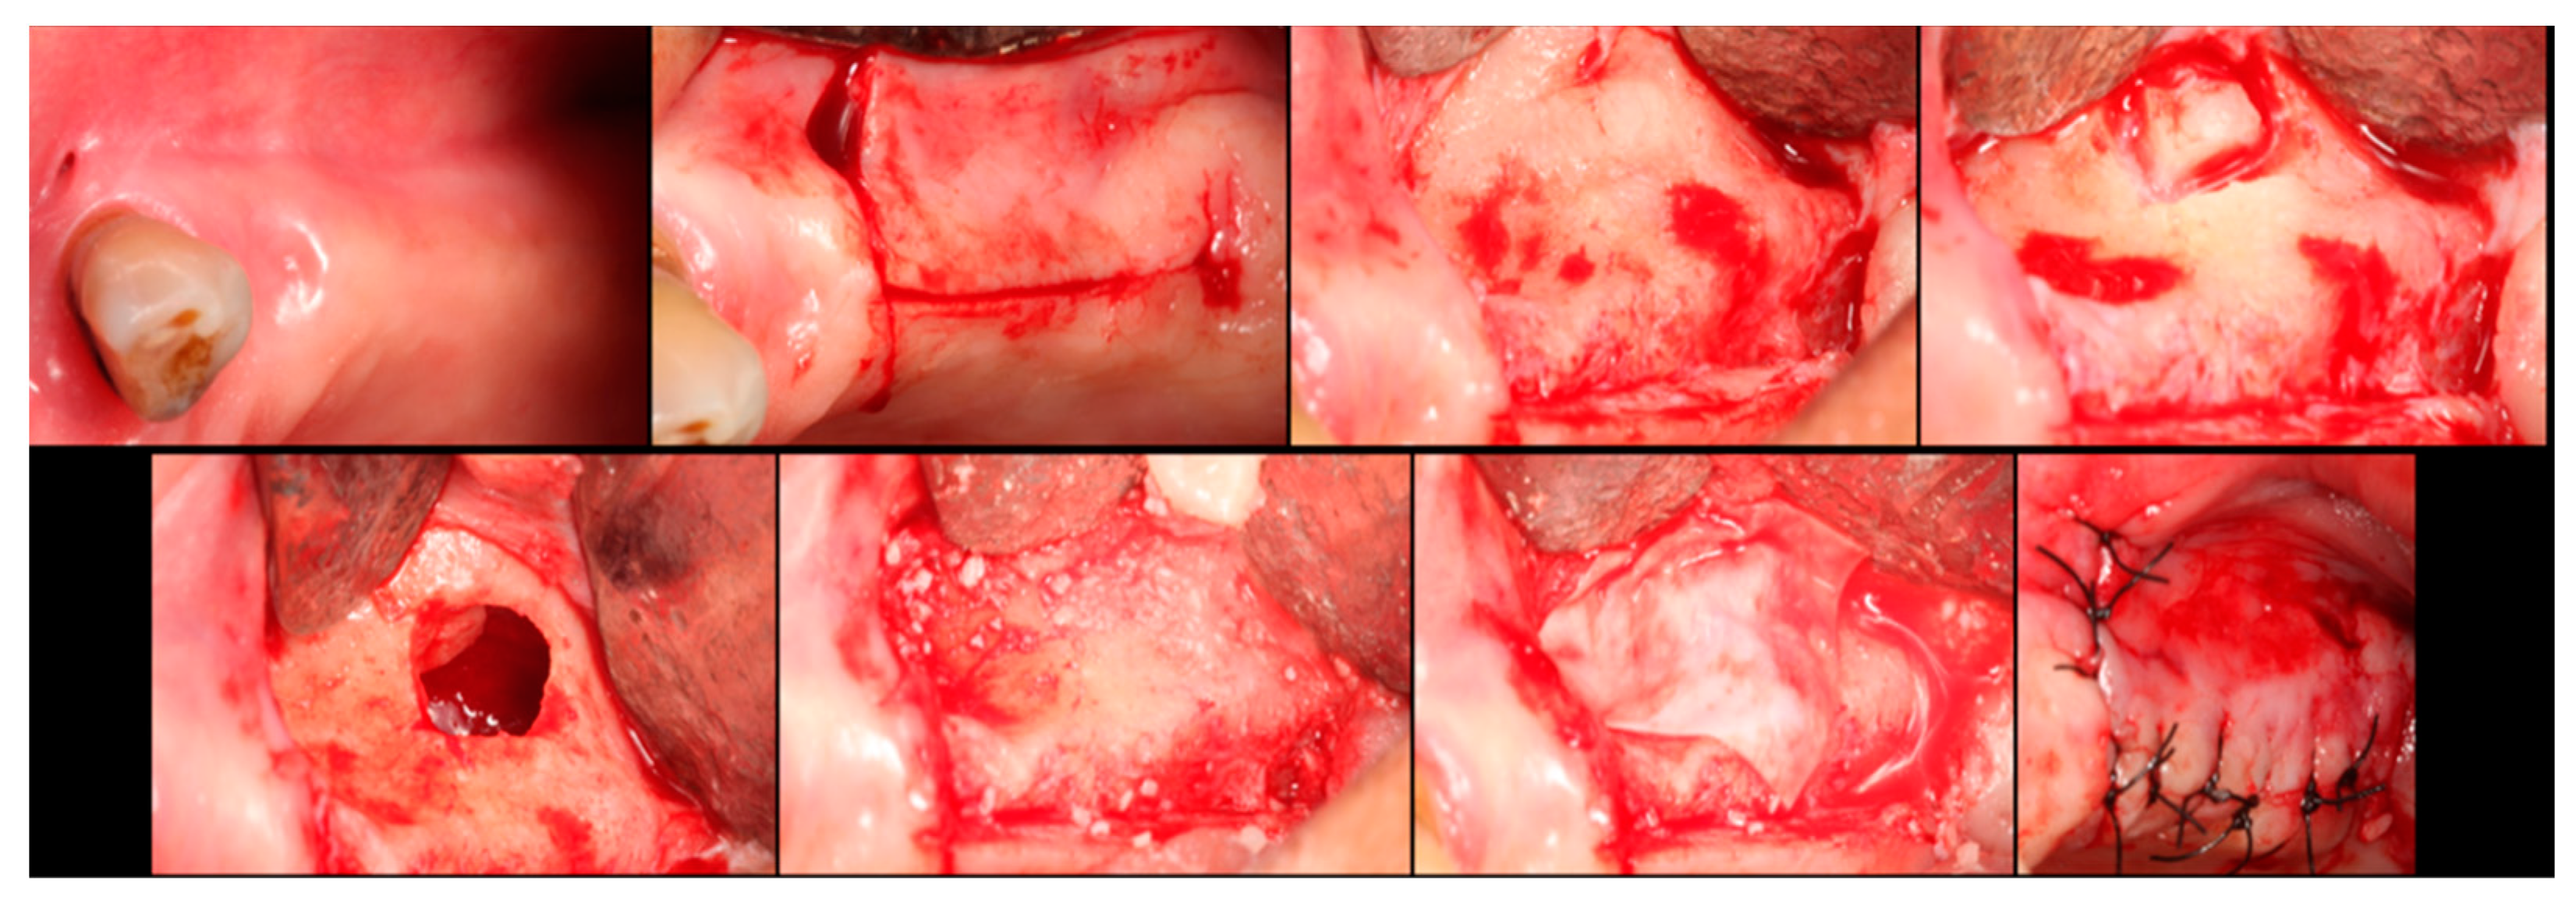

The surgical process, performed by the same surgeon, involved local anesthesia followed by incisions, flap detachment, osteotomy, and membrane elevation. Autologous bone from the mandibular branch (Figure 1) or the mental symphysis (Figure 2), or a porcine xenograft (Figure 3) were used as the graft materials for sinus augmentation. The protocol for this study involved using either two or three syringes of Oteobiol MP3, delivering a volume of approximately 2 to 3 cc per sinus. The contralateral sinus received a similar amount of autologous bone, either from the mental region (desmal with probably some bone of enchondral origin) or the mandibular ramus (desmal origin). Figure 3 and Figure 4 depict one example from each side of maxillary sinus augmentation treatment. Post surgery, the patients followed a prescribed protocol. After six months, a follow-up CT scan was conducted, and dental implants were placed. The final phase involved inserting healing abutments or prostheses, ensuring that no tooth–implant connections were established [20].

Figure 4. Step-by-step surgical demonstration of maxillary sinus elevation with autologous bone graft. In the first row, left to right: incision in the fourth quadrant, flap detachment, and lateral osteotomy. In the second row, left to right: accessing the sinus, filling with autograft, collagen membrane positioning, and sutures.